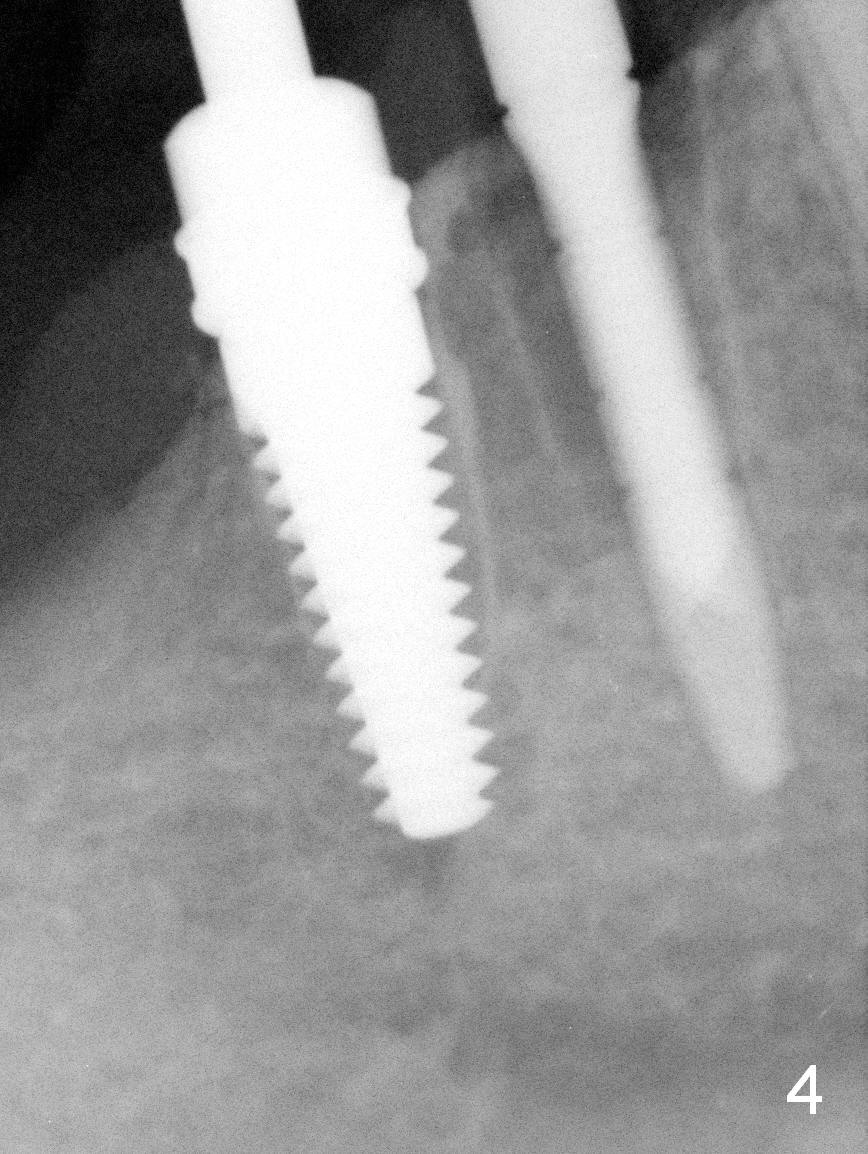

After restoring the implant at the site of #20, the patient returns for #28,29 implant placement (Fig.1,2). Bone level and distance from the Mental Loop (Fig.2 red dashed line) are different. It appears that longer implant can be placed at #28 than that at #29. Parallel pins are placed after initial osteotomy (Fig.3), it appears that the osteotomy at #29 should be moved mesially (arrow). Next PA shows that the position of the osteotomy at #29 is corrected (Fig.4). The position of the implants (4.5x17, 4.5x14 mm) appears ideal (Fig.5). After preparation for an immediate provisional, bone graft is placed in the remaining socket space (Fig.6 *). The splinted provisional is temporarily placed (Fig.7 P). The implant at #29 seems to be buccally placed. After CBCT confirmation, it should be removed for replacement. In addition to moving the osteotomy lingually, there is apparent space (~3 mm) to extend the osteotomy apcially for primary stability (Fig.8 arrow). The apical diameter of the implant is 3 mm.